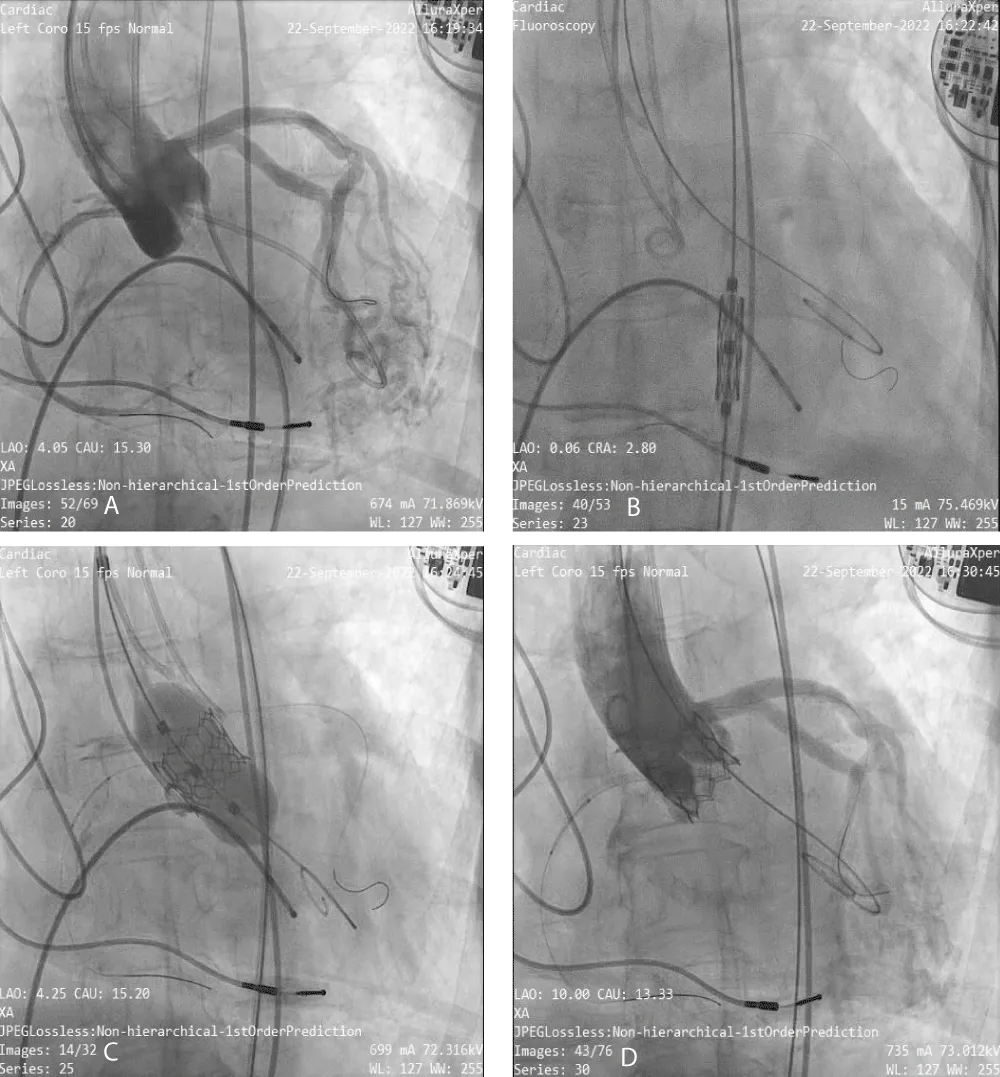

Download Image

The TAVR was performed in the patient under conscious sedation and angiographic imaging guidance with transthoracic echo-doppler monitoring. The right and left femoral arteries, and right femoral vein were cannulated. Through the right femoral vein access, the Temporary Pacemaker (TPI) was positioned in the right ventricle. As a marker for valve installation and to permit arteriography for positioning during the TAVR treatment, a 6-Fr graded pigtail catheter was inserted into the noncoronary sinus via the right femoral artery. Following the completion of all arterial and venous accesses, intravenous unfractionated heparin was delivered to achieve the necessary activated clotting time of > 250 s. The right femoral artery was used to insert a soft 0.035”- J-tipped wire into the descending thoracic aorta followed by performing a pre-closure using a single suture-mediated closure device (Perclose ProGlide®, Abbott Laboratories, Abbott Park, IL, USA) while maintaining arterial access through the J-tipped guidewire. Serial dilatations were performed using the 10-Fr/12-Fr dilator, which was followed by the insertion of the 14-Fr Python Introducer Sheath into the right femoral artery. To cross the valve, a 6-Fr AL-1 catheter was inserted through the valve delivery sheath, and a 0.035”- J-tipped guidewire was inserted and swapped for a 0.035 - inch straight-tip wire (Radiofocus® Guidewire M, Terumo Corporation., Tokyo, Japan). After crossing, the straight-tip wire was replaced with a 300-cm J-tipped wire following which, the AL-1 catheter was withdrawn and replaced with a 6-Fr angled pigtail catheter. Subsequently, a stiff guidewire SAFARI 2™ (Boston Scientific, Marlborough, MA, USA) was inserted through the angled pigtail catheter into the left ventricle with the guidewire’s transition point held above the apex and pointing away from the ventricular wall. A 20 mm BE Myval THV implant was crimped over the Navigator THV delivery system and deployed with rapid pacing through the TPI (Figure 2). Immediately after the procedure, peak and mean PG improved to 30 mmHg (baseline: 61 mmHg) and 16 mmHg (baseline: 38 mmHg), respectively.

Figure 2: Angiographic images of Myval THV Implantation- A) Baseline Aortogram, B) Myval THV Navigation, C) Myval Deployment and D) Final aortogram with no PVL.